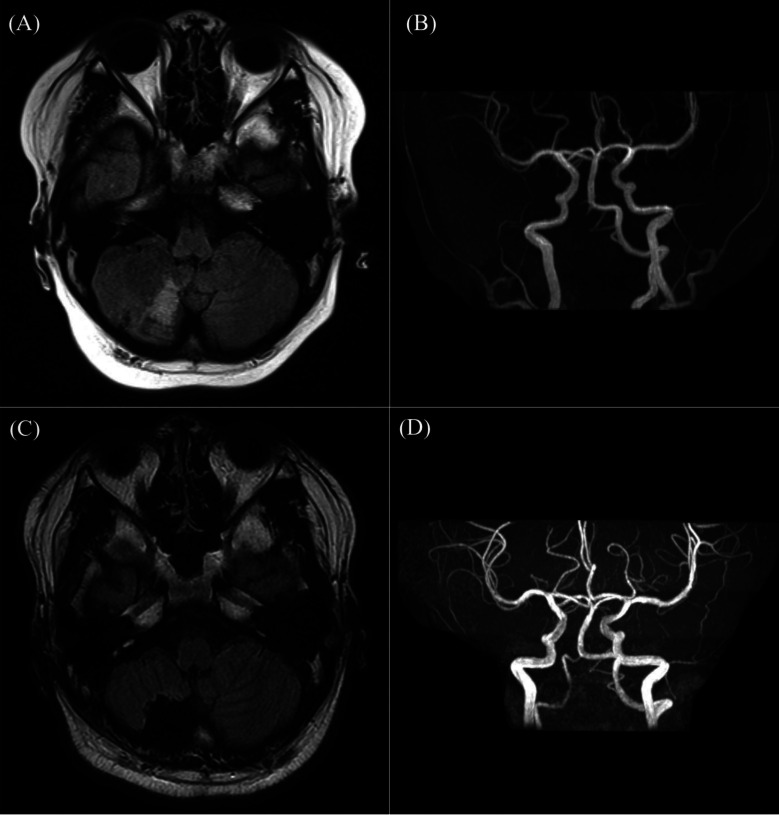

中枢性睡眠呼吸暂停(CSA)在大龄儿童中很少见。虽然中枢性睡眠呼吸暂停大多由神经系统疾病(如Chiari畸形)引起,但肥胖儿童中中枢性睡眠呼吸暂停的发生率明显更高。在此,我们描述了一个 14 岁男孩的病例,他因严重肥胖和 8 岁时的外伤性侧髓综合征病史而继发 CSA。多导睡眠监测显示他患有严重的睡眠呼吸暂停综合征,呼吸暂停-低通气指数为每小时 41.4,中枢性呼吸暂停指数为每小时 8.9。头部磁共振成像显示没有新的脑干或小脑梗塞,但小脑梗塞的旧病依然存在。肥胖主要与阻塞性睡眠呼吸暂停有关。然而,肥胖会导致咽部塌陷,胸腔容积减少导致氧气储备减少,从而抑制呼吸中枢的刺激,导致 CSA。由于头部受伤后遗症导致的呼吸中枢紊乱在急性期后有所改善,因此肥胖被认为是本病例中 CSA 的病因。因此,严重肥胖的儿童可能需要对 CSA 进行监测。

Central sleep apnea (CSA) is rare in older children. Although CSA mostly arises from neurological diseases such as Chiari malformation, the frequency of CSA is significantly higher in obese children. Herein, we describe the case of a 14-yr-old boy who presented with CSA secondary to severe obesity and a history of traumatic lateral medullary syndrome at 8 yr of age. Polysomnography revealed severe sleep apnea syndrome with apnea-hypopnea index of 41.4 per hour and central apnea index of 8.9 per hour. Magnetic resonance imaging of the head showed no new brainstem or cerebellar infarcts; however, old changes in the cerebellar infarction persisted. Obesity is primarily associated with obstructive sleep apnea. However, obesity can result in CSA through pharyngeal collapse and the reduction of oxygen reserves caused by reduced thoracic volume, which suppresses respiratory center stimulation. Because the respiratory center disorder owing to head injury sequelae improved after the acute stage, obesity was deemed the cause of CSA in this case. Hence, children with severe obesity may require CSA monitoring.